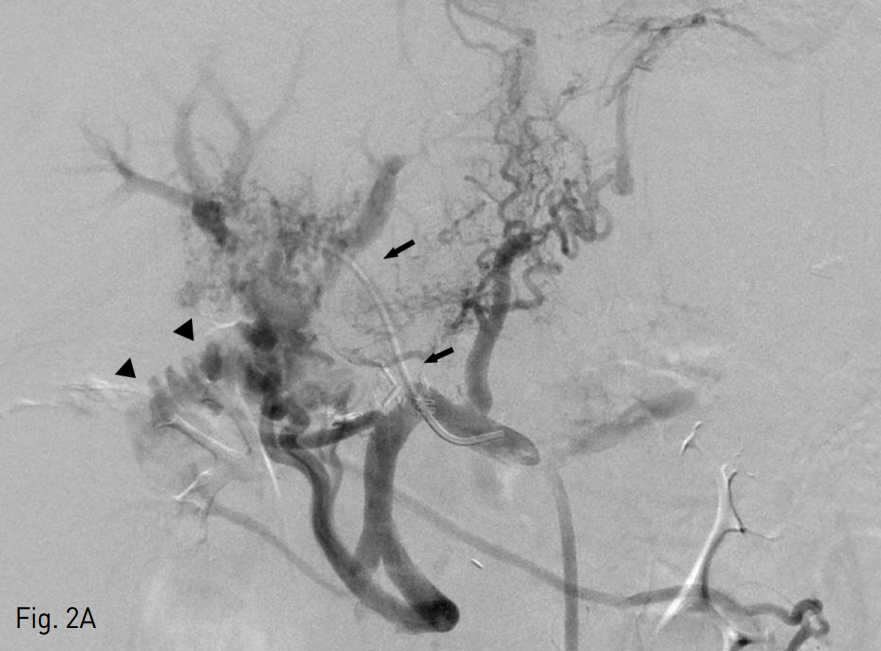

Fig. 3

A. Second transhepatic portogram with microcatheter shows active contrast media leakage to jejunum (arrows)

B. Seletive embolization with microcoils and recanalization with balloon dilation and stent placement were performed and portogram shows some residual cavernous transformation and patent portal vein flow.